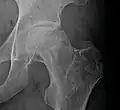

A variety of methods may be used to treat[5] the most common being the total hip replacement (THR). However, THRs have a number of downsides including long recovery times and the life spans of the hip joints (often around 20 to 30 years[22]). THRs are an effective means of treatment in the older population; however, in younger people, they may wear out before the end of a person's life.[22]

Other techniques such as metal on metal resurfacing may not be suitable in all cases of avascular necrosis; its suitability depends on how much damage has occurred to the femoral head.[23] Bisphosphonates which reduce the rate of bone breakdown may prevent collapse (specifically of the hip) due to AVN.[24]